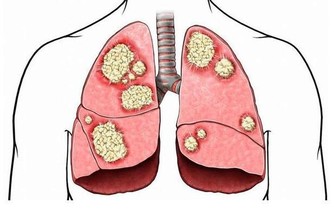

4、戒菸:煙草中的菸鹼可使心跳加快、血壓升高(過量吸煙又可使血壓下降)、心臟耗氧量增加、血管痙攣、血液流動異常以及血小板的粘附性增加。

5、控制體重:研究表明:體重增加10%,膽固醇平均增加18.5%,冠心病危險增加38%。體重增加20%,冠心病危險增加86%,有糖尿病的高血壓病人比沒有糖尿病的高血壓病人冠心病患病率增加1倍。

6、適量運動:積極參加適量的體育運動。維持經常性適當的運動,有利於增強心臟功能,促進身體正常的代謝,尤其對促進脂肪代謝,防止動脈粥樣硬化的發生有重要作用。